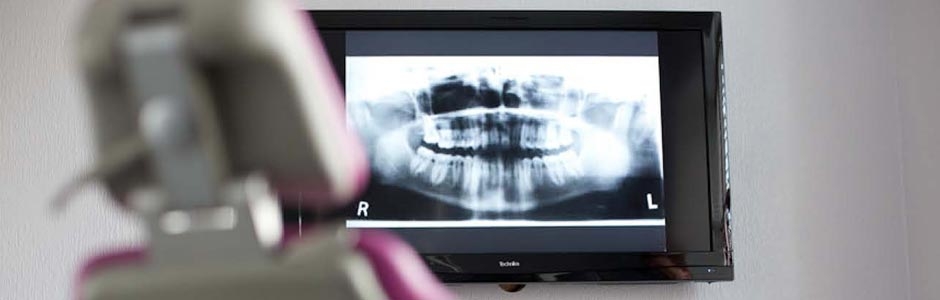

Dental Xrays play a vital role in the diagnosis of a range of dental problems such as finding hidden dental structures, cavities and bone loss that would be impossible to identify during a visual dental examination. Thanks to the advancements in science and technology, digital radiography has made the process of taking dental Xrays much faster and safer. With digital radiography, our dentists are able to provide excellent diagnosis to your dental problems in a really short time.

A welcoming alternative to conventional dental Xrays, digital radiography employs digital Xray sensors instead of photographic films. In this process, a digital image capturing device is used to snap the images of your teeth by inserting a sensor into your mouth. Although this process is very much similar to the traditional method, the sensor used in digital radiography is electronic and will be connected to a computer. So as soon as the dental Xray is taken, the image will be projected on the computer screen, available for immediate examination. Digital radiography can be used to take both intraoral as well as extra-oral xrays.

Superior quality images: Unlike the conventional Xray method, digital radiography offers the superb possibility to magnify and enlarge the images, delivering outstanding visuals of your teeth structures. This enables dentists to easily spot even tiny tooth cavities, extra tooth growth and so on.